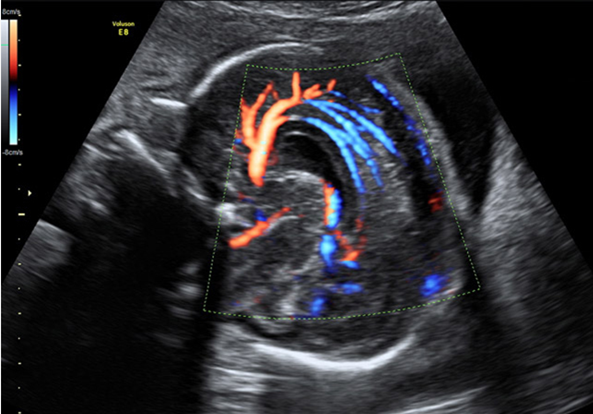

产科_胎儿颅脑_颅脑正中矢状面:正常胼周动脉